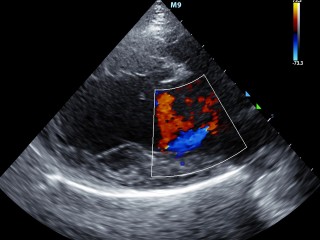

Echografie hart

Dierenarts Rianne Compagner maakt de hartecho's, zij heeft diverse cursussen en nascholingen hiervoor gevolgd.

Het hart in beeld

Hieronder zie je een aantal foto's van het hart.